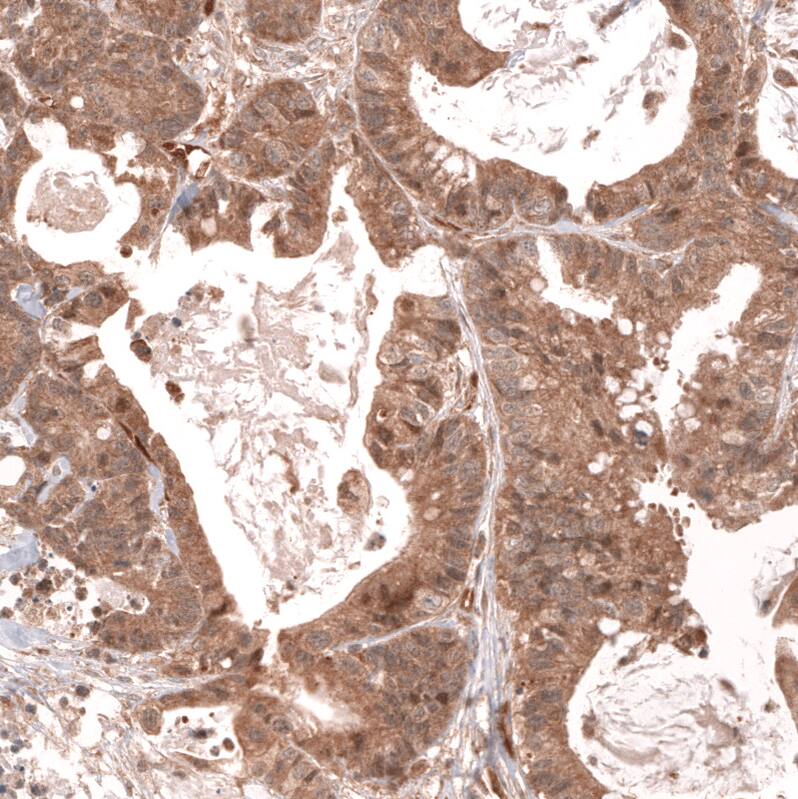

Staining of human ovarian cancer (papillary carcinoma) shows moderate to strong cytoplasmic and membranous positivity in tumor cells.